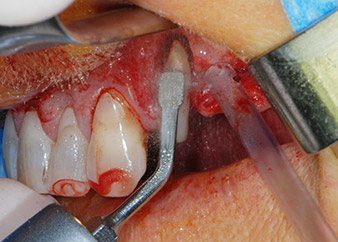

En primer lugar, en un intento por gestionar el problema endo-periodontal, el resto de la superficie radicular se desbridó con cuidado con un equipo piezoeléctrico (Piezomed de W&H, utilizado con el inserto S1 con forma de espátula, concebido en un principio para la erosión de la pared lateral del seno) (figura 4). A continuación, el ápice se erosionó con el mismo instrumento para eliminar el tejido apical infectado residual y reducir las posibles ramificaciones accesorias del canal radicular (apicectomía) (figura 5). No fue necesario realizar un retrorellleno, puesto que la obturación ortógrada se acababa de revisar.

Selección del equipo quirúrgico

Gracias a su acción precisa y suave, tanto el desbridamiento periodontal como la apicectomía de la pieza dental 24 se realizaron utilizando una unidad piezoeléctrica (Piezomed - W&H). Con el fin de evitar el riesgo de perder el diente, se necesitó una limpieza minuciosa, pero sin ejercer demasiada presión. El equipo también resultó útil para el desbridamiento del sitio quirúrgico, que funciona muy bien con el efecto de cavitación específico y las características de corte de la tecnología.